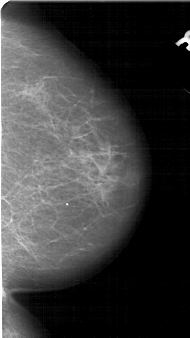

A_1651_1.RIGHT_CC

RIGHT_CC LINES 5056 PIXELS_PER_LINE 2836 BITS_PER_PIXEL 12 RESOLUTION 43.5 NON_OVERLAY